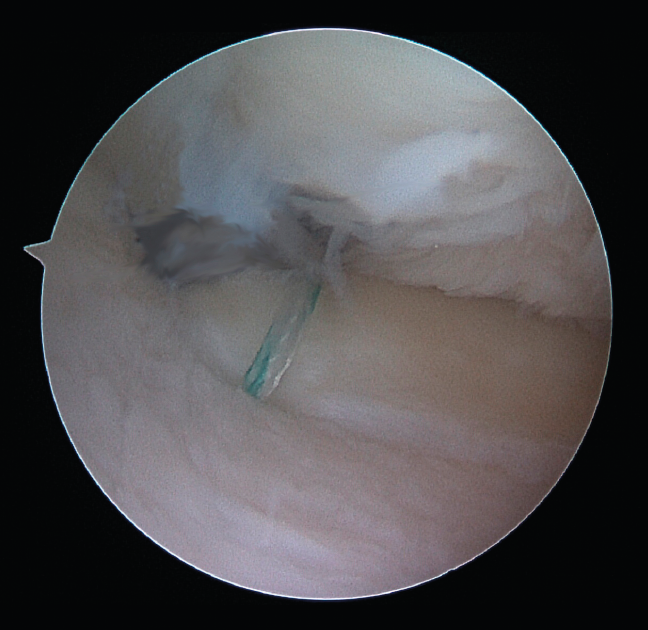

Figure 7. Final repair (right knee).

One of the patients in the standard guide group required modification of the perforation secondary to intraarticular exit of the Kirschner wire in a position different from that planned, due to positioning difficulties caused by the existence of a narrow intercondylar groove and prominent spines. The 3D printed guides adapted on both supports to the bone surface of the tibia and were precise in conducting the guide needles towards the planned position (Figures 6 and 7). There were no problems derived from friction between the metal of the needles and the bore of the customized guide, and handling was ergonomically satisfactory for the surgeon.